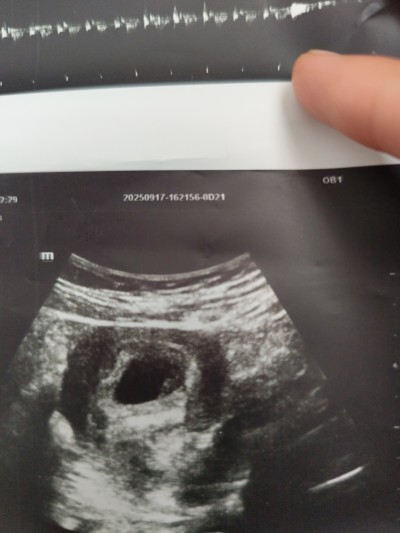

Gebelik haftası 7+1

Bazen kese göre değişiyor canım yuvarlak olursa  kız derler erkek olanda var şekilli olursa erkek olurdiyorlar  bende şekilli  bebeğim erkek 7 haftalık fotoğrafı vardı

Yani benim kesem şekilli mi

Şekilli gibi ama işte belli olmuyor canım dediğim gibi şekilli olup kız olanida var yuvarlak olup erkek olanıda en iyisi beklemek

Keseye göre erkek 😊